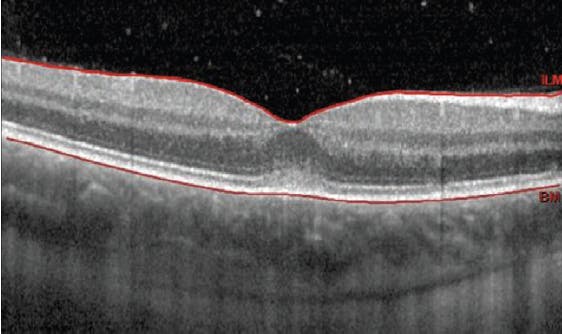

Her BCVA was 20/30-2 OD and 20/20 OS, and she now reported having a floater in her right eye that was blocking her vision. Entrance testing was normal and anterior slit-lamp examination was unremarkable. IOPs via Goldmann applanation tonometry were 14 mm Hg OU. A dilated fundus examination of the patient’s right eye revealed 1+ vitreous cell (Figure 1). Her vessels appeared normal. The patient’s optic nerve head had a granular appearance with trace nasal disc edema, and scattered focal hypopigmented lesions were visible in the periphery (Figure 2). All findings in the left eye were normal. OCT imaging illustrated the lesions as focal disruptions to the retinal pigment epithelium and ellipsoid zone, with no evidence of macular edema or subretinal fluid (Figure 3).

On additional evaluation, fundus autofluorescence showed several spots of hypoautofluorescence in the patient’s right eye. OCT angiography revealed multiple filling voids of nonperfusion in the choriocapillaris and choroid layer. The retina specialist supported the diagnosis of presumed MEWDS. Observation without treatment was recommended, and a follow-up appointment was scheduled for 2 months.

At the 2-month follow-up visit, the patient’s symptoms had resolved. Her distance VA was 20/20 OU. Anterior segment biomicroscopy and IOP were normal in both eyes. Posteriorly, the left eye remained unchanged. The disc edema and vitreous cells in the right eye were resolved and vessels were normal. The hypopigmented lesions were resolved, with subtle residual pigment clumping. The patient was released with no scheduled follow-up to monitor at annual eye exams.